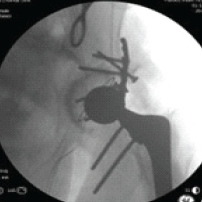

Intraoperative Traction for Cephalomedullary Nailing in Amputation Patients

Nicholas E. Runge , Jonathan T. Avon , Kishan C. Trivedi , Aaron J. Seidman

………………………………p.111-116